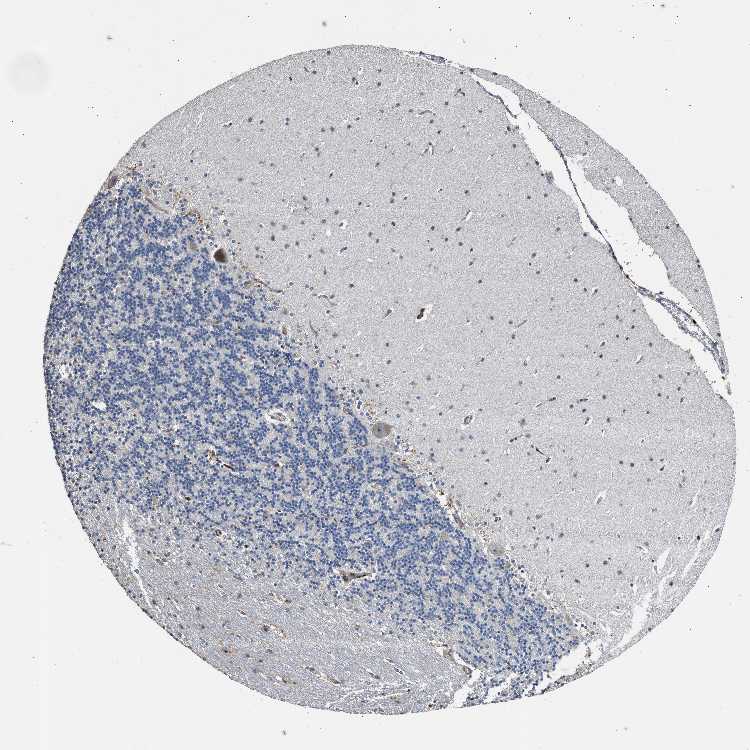

CEREBELLUM - Antibody stainingi

Antibody staining in the annotated cell types in the current human tissue is reported as not detected, low, medium, or high, based on conventional immunohistochemistry profiling in selected tissues. This score is based on the combination of the staining intensity and fraction of stained cells.

Each image is clickable and will lead to virtual microscopy that enables deeper exploration of all samples and also displays staining intensity scores, fraction scores and subcellular localization as well as patient and tissue information for each sample.

Antibody HPA003563Antibody HPA020432Antibody CAB004209

Purkinje cells Not detectedLowNot detected

Cells in granular layer Not detectedNot detectedNot detected

Cells in molecular layer Not detectedNot detectedNot detected